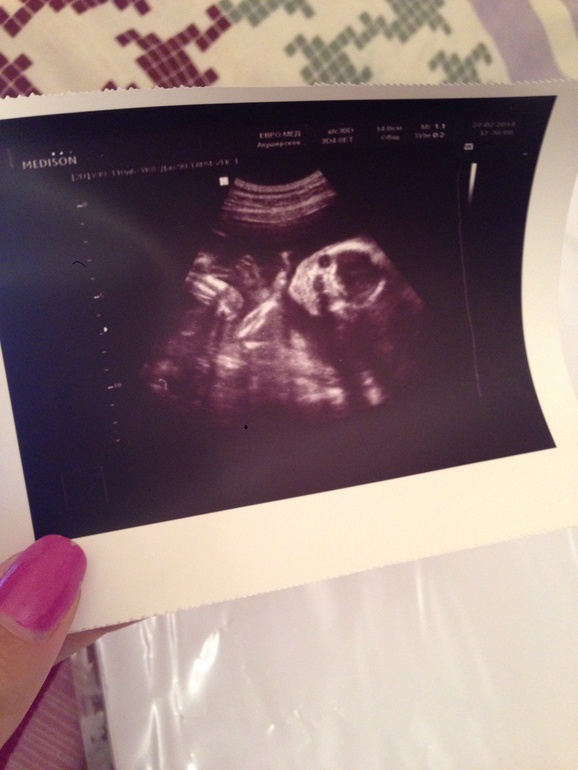

А вот и наша красавица)

(На фото справа головка, темные кружочки - это глазки, левее две ручки и ножка)

Акушерский срок 21 нед 1 день

Срок по УЗИ 19 нед 6 дней

БПР 4,5 см

Диаметр живота 4,7 см

Длина плечевой кости 2,9 см

Длина бедренной кости 3 см

Длина стопы 3 см

Лобно-затылочный размер головы 6 см

Мозжечок 1,9 см

Длина носовой кости 7,2 мм

Расширение лоханок обеих почек до 4 мм ( сказали что ничего страшного, но надо наблюдать)

25 см

318 грамм